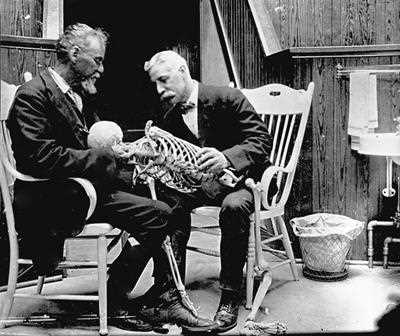

L’osteopatia nasce per merito del Dr. Andrew Taylor Styll (1828-1917) che visse tra il Kansas ed il Missuri. Styll fu un medico che si formò sul campo leggendo molti libri e studiando l’anatomia umana direttamente sui cadaveri degli indiani che lui stesso riesumava di nascosto. In seguito alla morte dei suoi tre figli per meningite e di una figlia per polmonite, intensificò i suoi studi a causa dell’insoddisfazione nei confronti della medicina tradizionale. Il suo principio si basava sul considerare il paziente malato nella sua totalità senza soffermarsi solamente sulla cura dei sintomi. Dopo una decina di anni presentò presso la Baker University, struttura che lui stesso contribuì a costruire, un suo primo lavoro sull’osteopatia che non venne assolutamente preso in considerazione (1874). La sua perseveranza, nonostante l’indifferenza del mondo medico, era premiata ed alimentata dal gradimento e dalla riconoscenza dei pazienti che aumentavano sempre di più attratti dal fatto che questo dottore curava senza l’utilizzo di farmaci. La prima scuola di osteopatia, l’American School of Osteopathy, fu ufficialmente fondata nel 1892 ed era composta da 21 allievi (uomini e donne) fra cui alcuni componenti della sua famiglia. Si cita che la vera e propria scoperta dell’osteopatia di Still fu alla tenera età di 10 anni e che fu casuale, quando, colpito da una forte emicrania, tese una corda tra due alberi e si appoggiò col capo come fosse un cuscino. Addormentatosi al suo risveglio il mal di testa era sparito, solo dopo anni di studi capì che la corda aveva inibito il funzionamento del nervo grande occipitale e permise un rilassamento totale del collo, aveva cioè sospeso l’attività dei grandi nervi occipitali, armonizzando il flusso del sangue arterioso. Aveva fatto dell’osteopatia!

Ad un certo punto della sua vita Still conobbe un uomo, tale John Martin Littlejohn.

John Martin nacque in Scozia nel 1865, uomo dall’intelletto fenomenale ma dalla salute cagionevole. Soffriva infatti di gravi emorragie alla gola tanto che un medico luminare dell’epoca gli consigliò di emigrare in paesi dai climi più caldi dandogli pochi mesi di vita. John Martin partì per l’America dove, sentendo parlare del Dr. Still, decise di farsi trattare non avendo nulla da perdere. Guarì completamente e decise di intraprenderne gli studi osteopatici divenendo discepolo diretto del Dr. Still. Entrambi si dedicarono alla ricerca, facendo diversi esperimenti e perfezionando sempre di più l’arte di guarire con le mani.